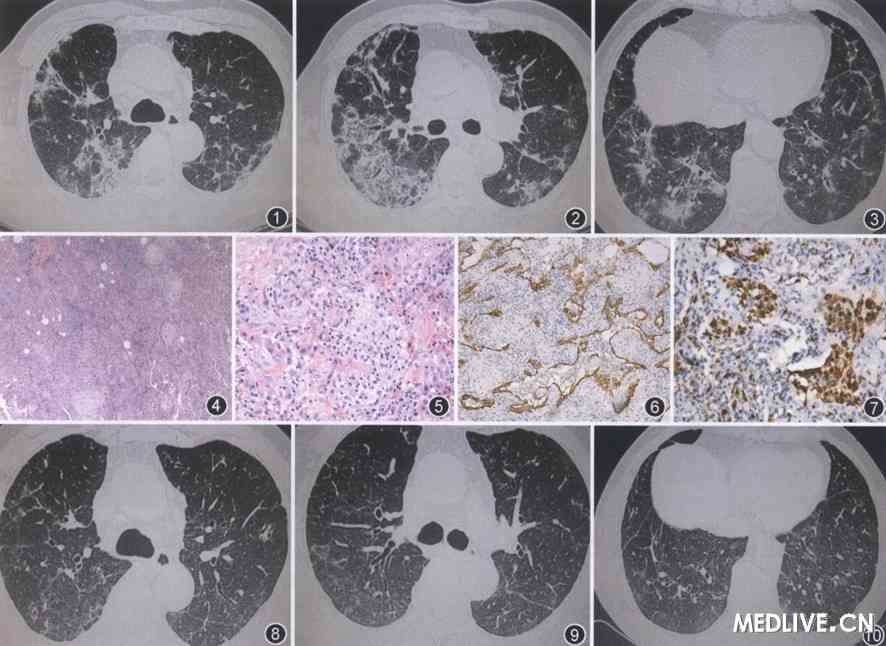

似肺癌的结节样病灶; 2011年6月23日肺部ct示双肺间质性病变伴

肺部肿瘤ct图片

肺部肿瘤ct

肺部肿瘤ct怎么看图解

肺部肿瘤图片ct光片

肺部肿瘤ct图片显示图